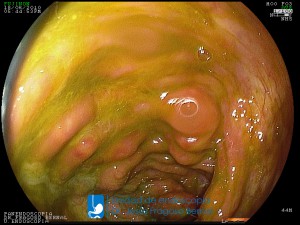

La Unidad de Endoscopía fue creada en 2002 por el Dr. Jesús Fragoso Bernal, es pionera en el estado por la utilización de la tecnología más avanzada, que nos permite ofrecer servicios integrales de diagnóstico y tratamiento para las enfermedades del aparato digestivo.

El profesionalismo de nuestro personal, altamente especializado, se distingue por la calidad y calidez de nuestros servicios con el objetivo de brindar una atención de excelencia en el ambiente más confortable para comodidad y seguridad de nuestros pacientes.

"La Unidad de Endoscopía se ha caracterizado por un progreso continuo desde su inicio marcando la pauta en los procedimientos endoscópicos en el estado de Tlaxcala y estando siempre a la vanguardia tecnológica."